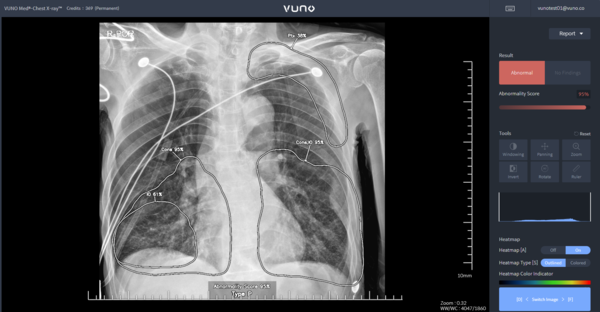

뷰노는 인공지능(AI) 기반 흉부 X-ray 판독 및 소견 검출 의료기기 ‘뷰노 메드-체스트 엑스레이(VUNO Med-Chest X-ray, 이하 Chest X-ray)’가 혁신의료기술로 승인돼 오는 6월 1일부터 비급여 시장에 진입한다고 15일 밝혔다.

보건복지부의 혁신의료기술 관련 고시 확정에 따라 Chest X-ray는 2025년 6월 1일부터 2028년 5월 31일까지 3년간 임상 현장에서 사용이 가능하다. 이 제품은 흉부 X-ray 영상을 분석해 결절, 경화, 간질성 음영, 흉막 삼출, 기흉 등 5개 이상 소견 유무를 검출하고, 소견 조합을 통해 폐렴과 폐결핵 두 가지 질환을 선별하는 진단 보조 소프트웨어다.